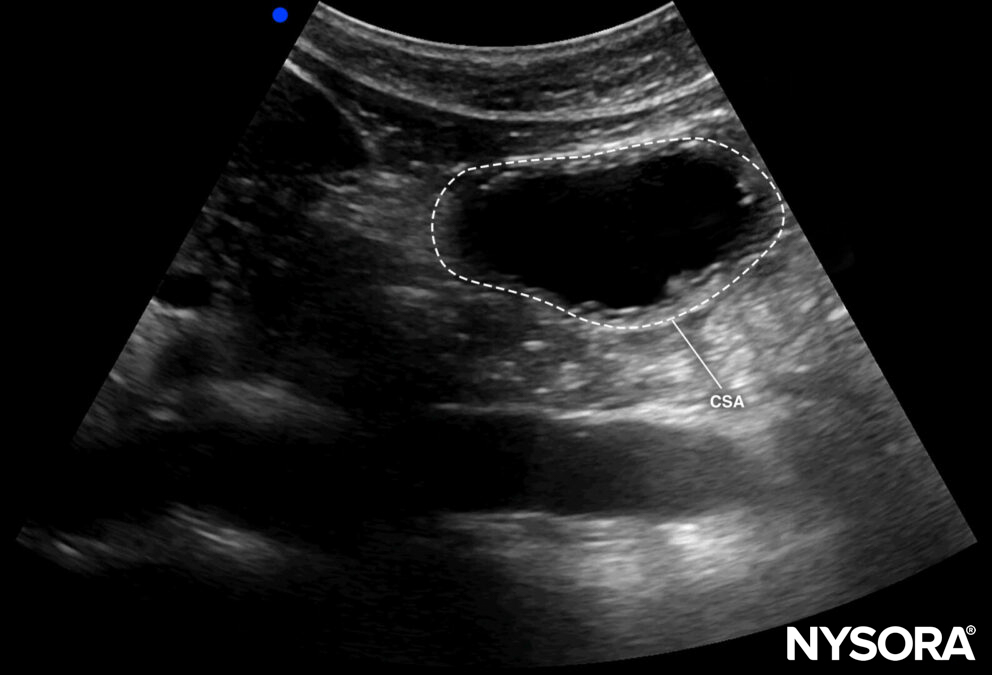

- If fluid content is visualized in the right lateral decubitus position, measure the cross-sectional area (CSA) by tracing the outer layer of the antrum or the serosa.

Cross-sectional area of the antrum.

- By using the CSA and the age of the patient, the volume can be estimated according to the formula:

Gastric volume = 27.0 + (14.6) x (CSA of antrum in right lateral decubitus position) – 1.28 x age

- If the fluid content is >1.5 mL/kg, the stomach is considered at risk for aspiration or full (grade 2).

- A fluid content < 1.5 mL/kg is compatible with a fasting state (grade 1).

- In case the ultrasound machine does not have a free tracing tool to measure the CSA, the area can be calculated by using two perpendicular diameters and the formula of the area of an ellipse: CSA = (anteroposterior diameter × craniocaudal diameter × π) / 4

- No peristaltic movements should be present during the measurement.